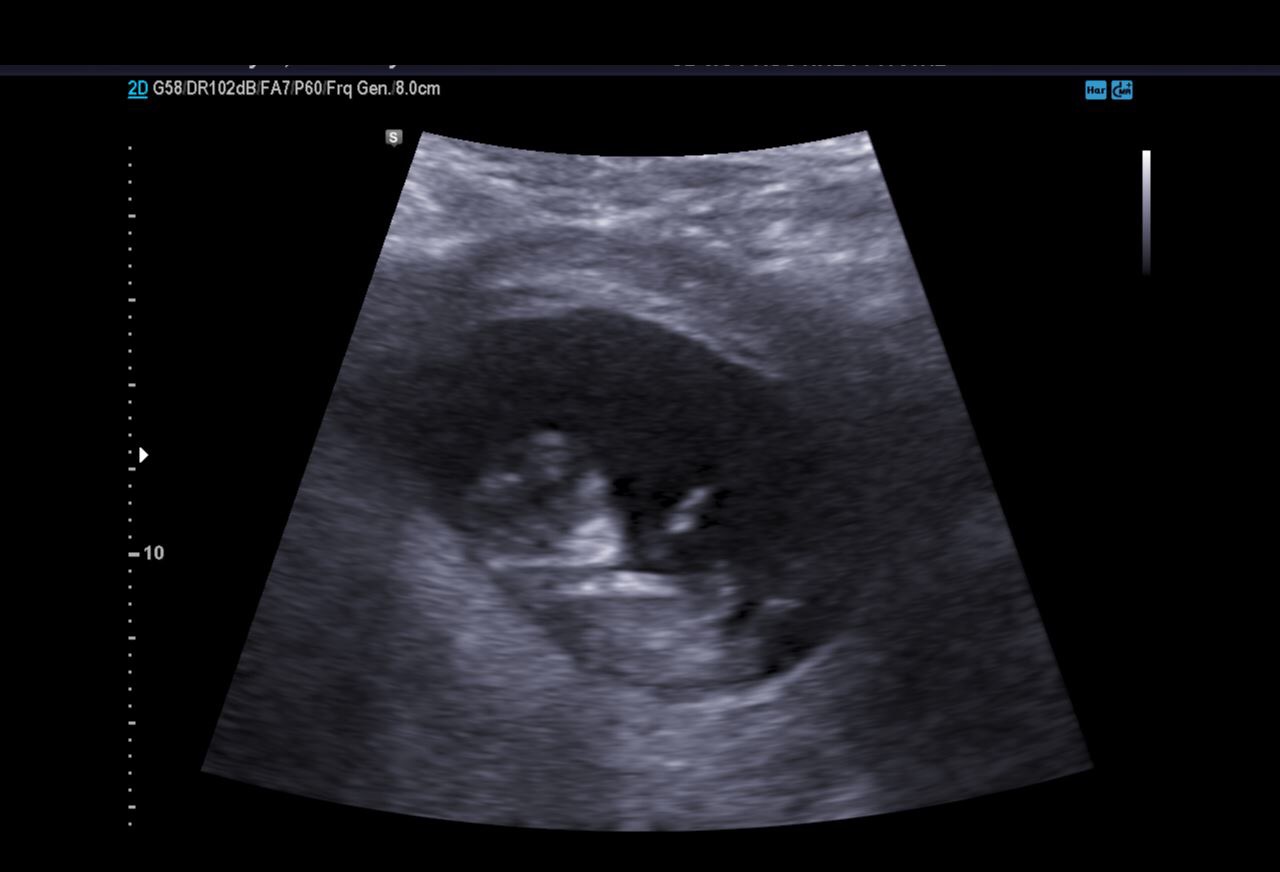

Our ultrasound looked great; little babe was just hanging out in there. Toward the end of the scan, baby started to move and we were able to get a few good photos where you can actually see the baby’s arms and legs.

I am still very much in shock that this is our life again, but seeing baby dancing around in there helped to hammer home the fact I think. They said everything looked good, and that we were measuring right on track. They said our due date was 3.23.18, with delivery at 37 weeks that will put our due date around 3.2.18.